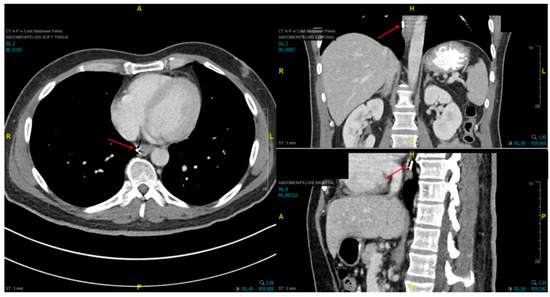

2.2. Distant and Locoregional Staging

- Flamen, P.; Lerut, A.; Van Cutsem, E.; De Wever, W.; Peeters, M.; Stroobants, S.; Dupont, P.; Bormans, G.; Hiele, M.; De Leyn, P.; et al. Utility of Positron Emission Tomography for the Staging of Patients With Potentially Operable Esophageal Carcinoma. J. Clin. Oncol. 2000, 18, 3202–3210. [Google Scholar] [CrossRef] [PubMed]